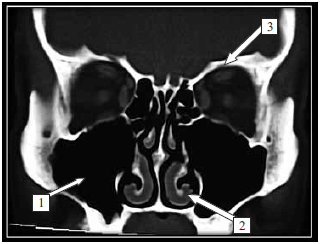

Observe o que segue:

Na imagem radiológica, as estruturas/regiões sinalizadas são, correta e respectivamente,